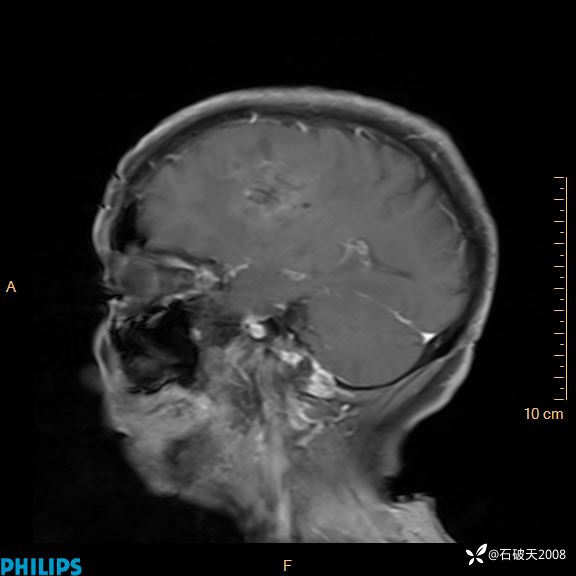

2024.2.21MR

增强矢状位